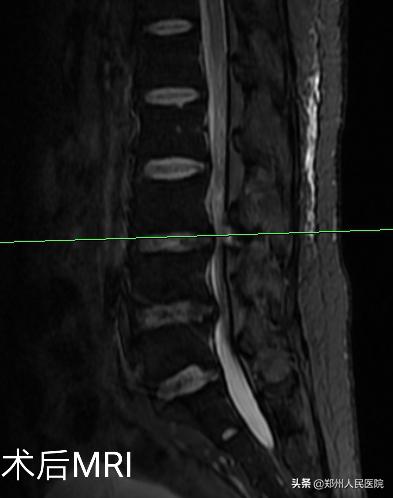

在度过神经水肿期后,小葛的疼痛便消失了大半,由于手术对骨质的破坏很小,脊柱的稳定性得以最大程度的保留,手术后3天小葛就可以在腰部支具的辅助固定下行走活动,往日开朗的笑容又重新回到他的脸上。

为刘叔进行的“单侧双通道UBE脊柱内镜术”在不足两个小时后顺利结束,术中麻醉效果极佳,出血量只有数十毫升,清晰放大的视野下,突出的髓核及增厚的黄韧带完全摘除,骨性狭窄磨钻安全扩大减压,偶尔出现的小出血点也在射频刀头的控制下立即止血,轻松漂浮的神经根又重新出现了。

手术后,田明波主任问刘叔手术前后的感受,他只说了一句话,“要知道这个微创手术效果这么好,真是该早点来手术”。